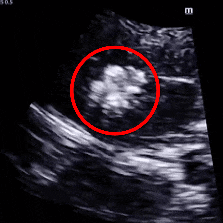

经食道心脏超声:四腔心切面缺口径宽约0.35cm,缺损边缘距二尖瓣环约2.1cm,距房顶约2.5cm,大动脉短轴切面缺口经宽0.36cm,主动脉后方无残边。双房切面缺口径约0.35cm,缺损边缘距上腔静脉约2.6cm,距下腔静脉约2.7cm。CDFI:房间隔连续中断处见左向右分流信号。

TEE可见房间隔中断出左向右分流

TEE测量缺损大小

肺动静脉CTA未见异常;经食道超声检查明确为小房缺,缺损直径约0.35cm。